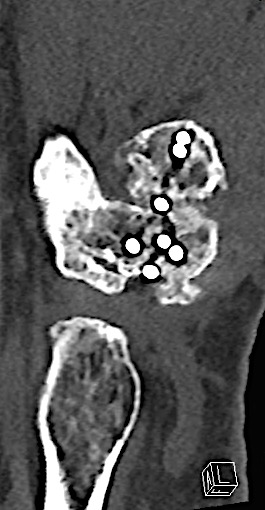

Case 1:

A 64-year-old male suffered a multi-fragmentary fracture of his right thumb metacarpal (Fig 1). An adapted 12-hole strut plate from the variable angle locking hand system was the implant of choice for fixation (Figs 2 - 4).

The strut plate provided good stability in a comminuted extraaricular fracture pattern and enables immediate mobilization. Bone callus formation was not witnessed during the healing process.